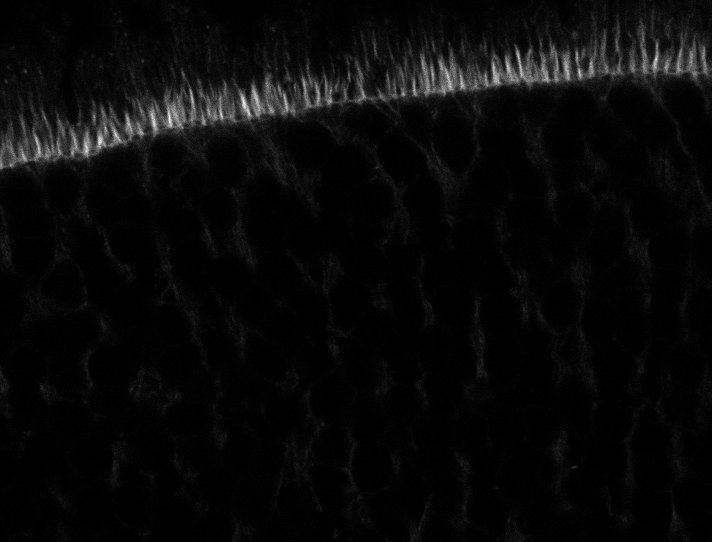

Actin